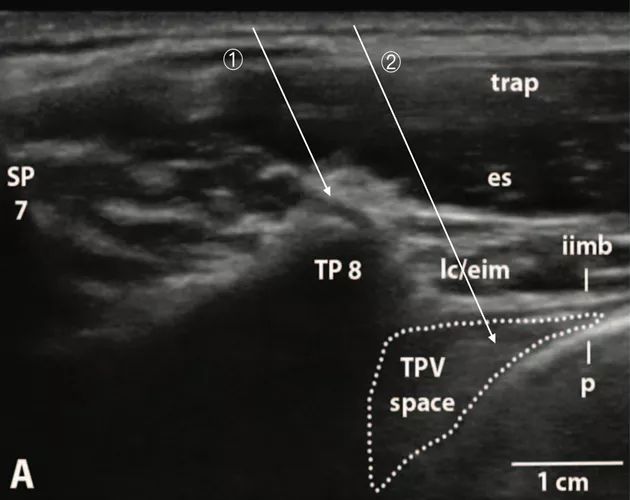

答:超声关节突水平的椎旁间隙较肋横突水平的椎旁间隙更宽,操作时更容易避开横突和肋骨,针尖更容易到达目标区域。下图[2]为肋横突水平椎旁间隙的超声扫查图像。如经肋横突水平外向平面内进针,可能会因针尖抵住横突(TP)而无法进一步深入(①),或者虽然避开了横突,但因抵达胸椎旁间隙的外侧角(②),非最佳目标区域。

(Anesthesiology 2015; 123:459-74)